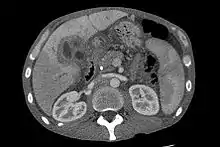

CT scan showing cholangiocarcinoma

Ultrasound of the liver and biliary tree is often used as the initial imaging modality in people with suspected obstructive jaundice.[49][50] Ultrasound can identify obstruction and ductal dilatation and, in some cases, may be sufficient to diagnose cholangiocarcinoma.[51] Computed tomography (CT) scanning may also play an important role in the diagnosis of cholangiocarcinoma.[52][53][54]